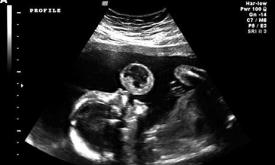

Ieri dupa-amiaza am mers la control...am facut ecografia de 34 de saptamani....Am avut emotii mari pentru ca trecuse ceva timp de cand nu-l mai vazusem pe bebe...Tati era si mai emotionat...si cand domnul profesor Tica i-a arata si ce il interesat pe el mai mult, organele genitale..,.tati s-a inmuiat si mai mult....Dupa ce a facut domnul doctor niste masuratori.....ni l-a arata si noua.....am vazut...manutele...si le tinea incrucisate, in dreptul fetei...motiv pentru care nu am reusit sa ii vedem decat un ochisor....micutul nu a vrut sa ne arate fata....cica e surpriza....AAAAA am mai vazut si o urechiusa....e cam clapaug...seamana cu tati....

In momentul in care i-am auzit inimioara batam si am si vazut-o....cu toate cele 4 camere, 2 atrii si 2 ventriculi...asta e bine...am crezut ca lesin....vroiam sa ii cer doctorului sa mai prelungeasca momentul....nu am cuvinte sa va povestesc.....Auurmat apoi rinichii, vezica urinara....piciorusele.....coastele...,.sira spinarii....in concluzie....il citez pe domnul Tica "este un baietel reusit....si este dezvoltat foarte bine, doar ca e cam smecheras...ne lasa sa vedem doar ce vrea el....".....La sfarsit ne-a spus ca are deja in jurl de 2,5 kg si ca mai are destul timp sa mai creasca.....